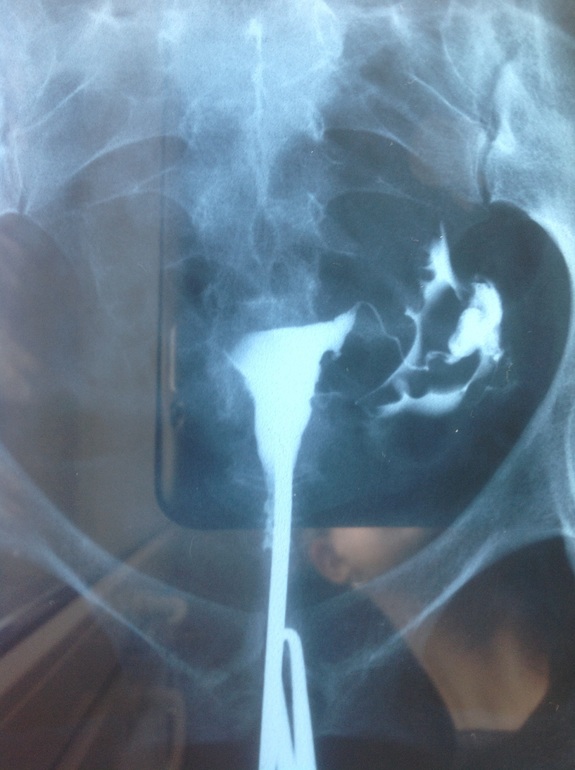

Результат ГСГ!!!!!

Здравствуйте девочки!!! Прошла сегодня ГСГ И ВОТ ЗЕЗУЛЬТАТ: кто сталкивался с таким?

инехию12 февраля была гистероскопия! Удалили полип и синехию!!!Девочки, кто сталкивался, подскажите пожалуйста, чем дело закончилось?!Заранее спасибо за ответы!!!

Это первая гистера!!! Декабрь 2014г

Это месяц назад!!! 12 февраля!!!